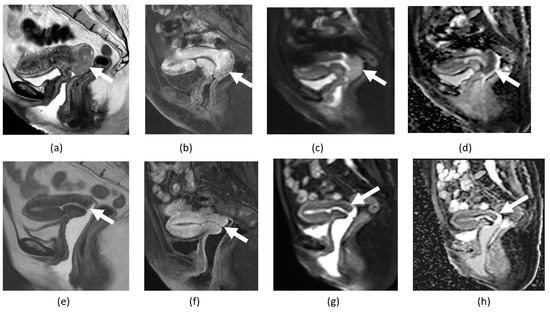

4.1. Cervical Cancer